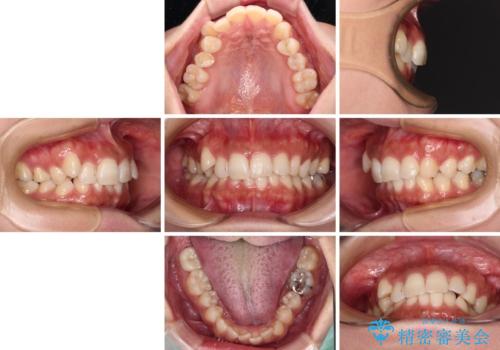

- 目立つ八重歯を気にして来院された患者様です。

上顎小臼歯を抜歯するかどうか悩みましたが、八重歯の後方に失活歯があること、治療前に上顎正中が概ね人中に合っていることから、右上第二小臼歯を抜歯することとしました。

片側での抜歯であると、正中が抜歯した方向にずれていくため、左上の奥歯を遠心移動させる目的でアンカースクリューと補助装置を併用した上で、ワイヤー装置にて矯正治療を行うこととしました。

上顎の正中位置をほぼ保った状態で、綺麗に仕上げることができました。